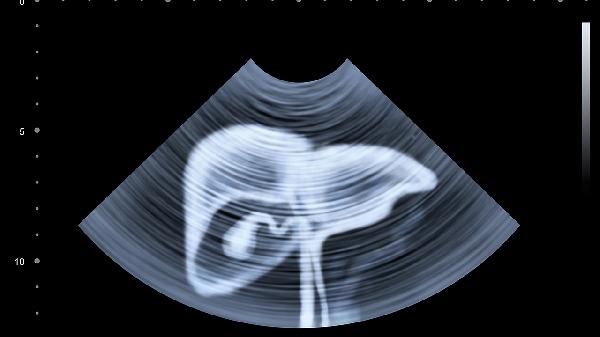

胆囊结石或细菌感染引发的炎症可能导致右上腹闷胀并向中上腹放射,高脂饮食后症状明显。超声检查可确诊,轻症可用消炎利胆片,急性发作需使用头孢克肟分散片抗感染,反复发作者需考虑腹腔镜胆囊切除术。